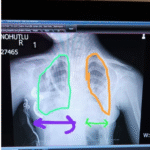

Thoracic dystrophies can lead to inadequate development of lung and chest organs causing respiratory distress in the form of “Asphyxiating Thoracic Dystrophy,” or it can manifest as “Fibrodysplasia Ossificans,” causing issues in toe and chest wall bones. The form often seen as “Asphyxiating Thoracic Dystrophy” has 22 different types. The most commonly known is “Jeune Syndrome.” Other well-known ones are Saldino-Noonan Syndrome, Majewski Syndrome, Mainzer-Saldino Syndrome, Beemer-Langer Syndrome, and Ellis-van Creveld Syndrome. The common findings in all phenotypes are inadequate development of the chest cage (thoracic hypoplasia) and shortened ribs, which can lead to various deformities in the chest wall.